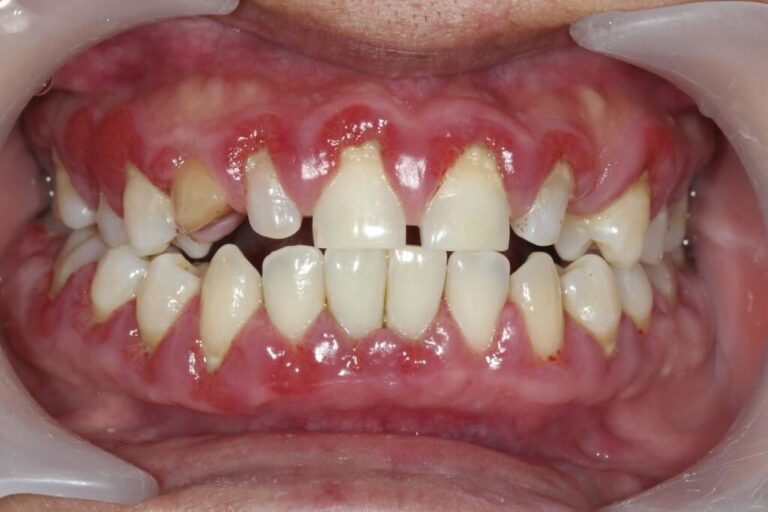

La gingivite, une inflammation des gencives, peut avoir des conséquences significatives sur la santé bucco-dentaire.

La principale cause de la gingivite est l’accumulation de plaque dentaire. Cette fine couche composée de bactéries et de débris alimentaires se forme constamment sur les dents. Si elle n’est pas éliminée efficacement par un brossage régulier, elle peut irriter les gencives, déclenchant ainsi une réaction inflammatoire.

D’autres facteurs peuvent contribuer à la gingivite, tels que le tabagisme, le diabète, les changements hormonaux (comme pendant la grossesse), et des conditions médicales sous-jacentes. Une alimentation déséquilibrée et des habitudes de vie peu saines peuvent également aggraver le risque de développer une gingivite.